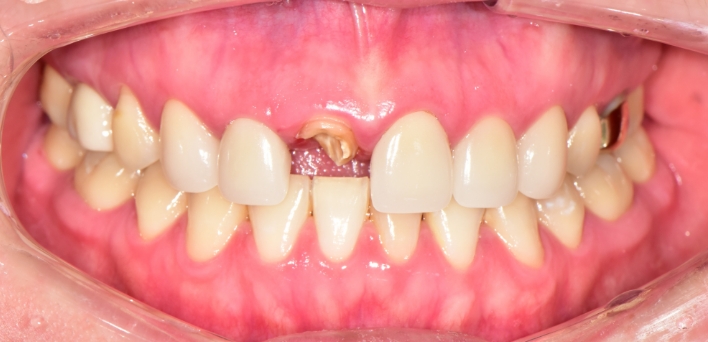

임플란트 : 손 ** 님 (50대)

Before Before

2020.02.30

After After

※ 더서울치과의원은 의료법을 준수하며 위 케이스는 실제 환자의 동의를 얻은 사례로 치료 전, 후가 동일한 환경에서 촬영되었습니다.

환자 케이스에 따라 부작용이 발생할 수 있습니다. 이 부분은 의료진의 충분한 상담과 체크를 통해 예방하고 줄일 수 있습니다.

[임플란트 부작용] 수술 후 관리가 소홀할 경우 출혈, 주위염 등의 부작용이 발생할 수 있어 구강 위생을 철저히 유지하고, 정기적인 검진을 통해 상태를 점검하는 것이 중요합니다.

환자 특징

환자 특징01무치악 상태

환자 특징02수년간 무치악으로 지내심

임플란트가 불가능할것이라

생각하고 내원

위, 아래 6개씩 식립

디지털 풀아치 임플란트